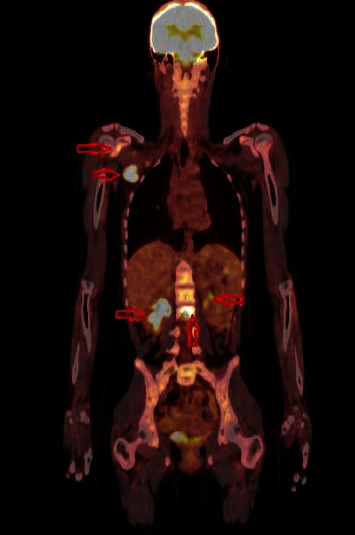

Cat scratch disease (CSD) typically presents as a self-limiting lymphadenopathy associated with a cat bite or scratch and commonly affects children and young adults. Atypical manifestations, involving the eyes, nervous system, heart, liver, spleen, skin, and musculoskeletal system, could be severe and difficult to diagnose, and they could occur in 5%-20% of the cases. Herein, we report an unusual case of CSD with multifocal osteomyelitis. A 15-year-old girl presented with right axillary lymphadenopathy. Since she had a history of cat scratch, azithromycin was started for CSD. Two days later, she was readmitted to our hospital with severe back pain which required differential diagnosis. Lumbar spinal magnetic resonance imaging (MRI) revealed multifocal vertebral osteomyelitis. The patient was hospitalized, and then teicoplanin and cefotaxime were added to the azithromycin therapy. After excluding the possible other causes, the definitive diagnosis of osteomyelitis secondary to CSD was made upon the combination of the MRI scan findings of the vertebrae, histopathological investigation of excisional right axillary biopsy, positron-emission tomography/computed tomography (PET/CT), and Bartonella henselae serologies. Atypical manifestations of CSD are widely variable; therefore, it should be kept in mind in the differential diagnosis of severe musculoskeletal pain and osteomyelitis.

猫抓病(CSD)通常表现为与猫咬伤或抓伤相关的自限性淋巴结病,常见于儿童和青壮年。非典型表现可累及眼睛、神经系统、心脏、肝脏、脾脏、皮肤和肌肉骨骼系统,病情严重且难以诊断,约占病例总数的5%-20%。在此,我们报告了一例不同寻常的 CSD 合并多灶性骨髓炎病例。一名 15 岁女孩因右腋窝淋巴结肿大就诊。由于她有猫抓病病史,医生开始使用阿奇霉素治疗 CSD。两天后,她因剧烈背痛再次入院,需要进行鉴别诊断。腰椎磁共振成像(MRI)显示她患有多灶性脊椎骨髓炎。患者住院后,在阿奇霉素治疗的基础上加用替考拉宁和头孢他啶。在排除了其他可能的病因后,结合椎体的核磁共振扫描结果、右腋窝切除活检的组织病理学检查、正电子发射断层扫描/计算机断层扫描(PET/CT)和鸡巴氏杆菌血清学检查,最终确诊为继发于 CSD 的骨髓炎。CSD 的非典型表现千变万化;因此,在鉴别诊断严重肌肉骨骼疼痛和骨髓炎时应牢记这一点。